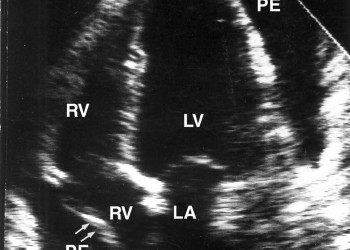

Apare la pacienţii cu insuficienţă renală cronică, în stadiul uremic, dar şi la cei cu nefropatii acute care asociază insuficienţă renală. Pericardita uremică este cel mai frecvent lichidiană, iar lichidul se reface rapid. Tratamentul este cel al cauzei – insuficienţa renală – dializă peritoneală şi hemodializă. Dacă apare tamponada cardiacă, se va practica pericardiocenteza evacuatorie sau pericardiotomia minimă cu drenaj.

Extensia neoplazică la pericard poate apărea de la cancere de vecinătate, de la adenopatii neoplazice de vecinătate sau prin metastazare la distanţă a unor cancere cu alte localizări (cancer bronhopulmonar, cancer mamar, limfoame). Pericardita neoplazică este de obicei lichidiană şi evoluează rapid către tamponadă pericardică. Tratamentul constă în administrarea pe cale sistemică şi prin instilare intrapericardică de citostatice. Este necesară şi efectuarea periodică de pericardiocenteze evacuatorii.